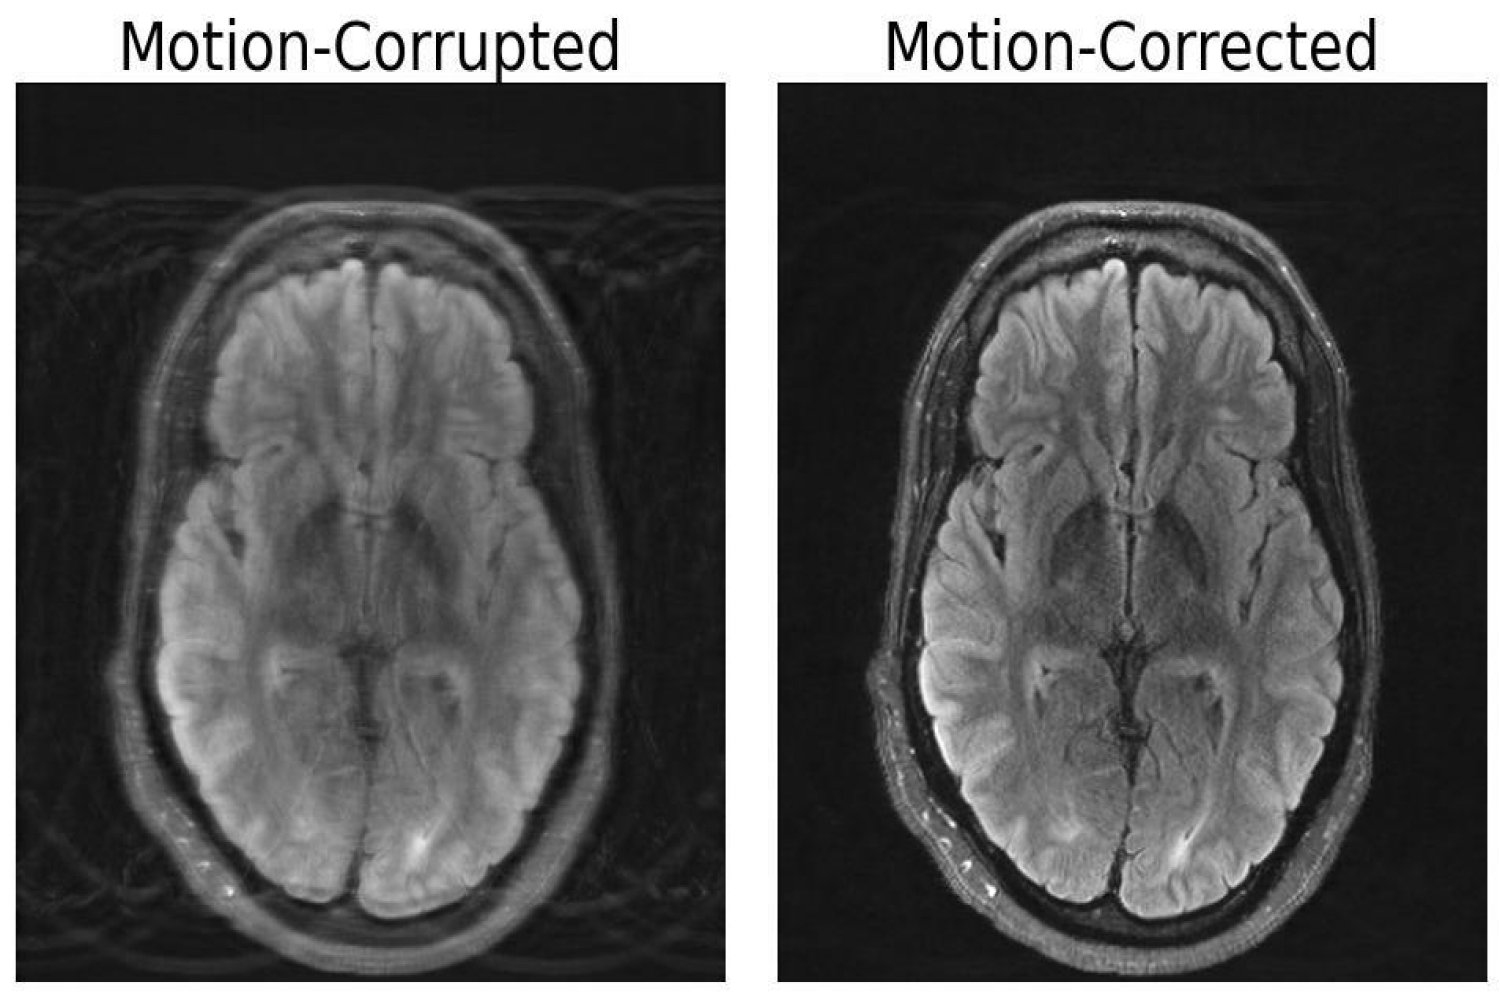

Compared to other imaging modalities like X-rays or CT scans, MRI scans provide high-quality soft tissue contrast. Unfortunately, MRI is highly sensitive to motion, with even the smallest of movements resulting in image artifacts. These artifacts put patients at risk of misdiagnoses or inappropriate treatment when critical details are obscured from the physician. But researchers at MIT may have developed a deep learning model capable of motion correction in brain MRI.

The paper, titled “Data Consistent Deep Rigid MRI Motion Correction,” was recently awarded best oral presentation at the Medical Imaging with Deep Learning conference (MIDL) in Nashville, Tennessee. The method computationally constructs a motion-free image from motion-corrupted data without changing anything about the scanning procedure. “Our aim was to combine physics-based modeling and deep learning to get the best of both worlds,” Singh says.

The importance of this combined approach lies within ensuring consistency between the image output and the actual measurements of what is being depicted, otherwise the model creates “hallucinations” — images that appear realistic, but are physically and spatially inaccurate, potentially worsening outcomes when it comes to diagnoses.